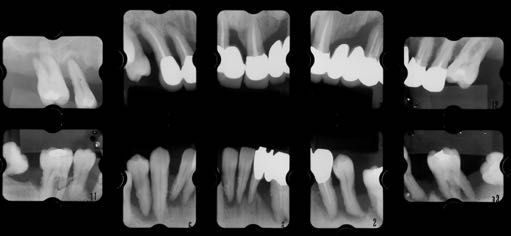

Degree of Difficulty +++

非常に治療難易度の高いケースである